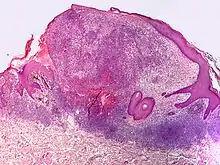

Small-cell melanoma

Small-cell melanoma, also known as melanoma with small nevus-like cells, is a cutaneous condition, a tumor that contains variably-sized, large nests of small melanocytes with hyperchromatic nuclei and prominent nucleoli.[1]